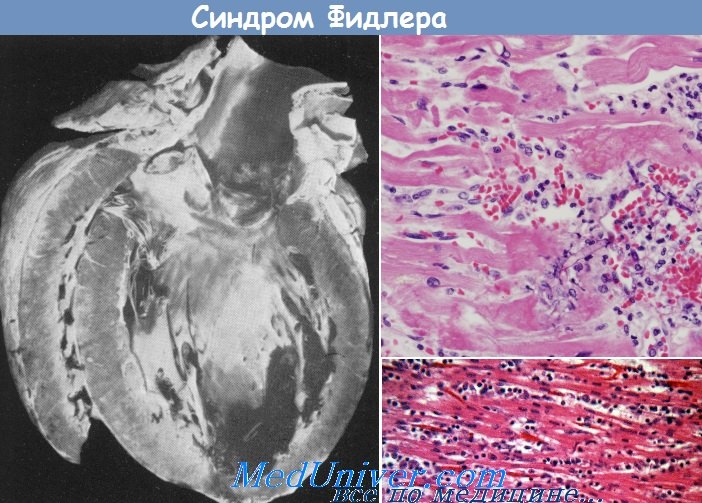

Межуточный миокардит: гистологические исследования